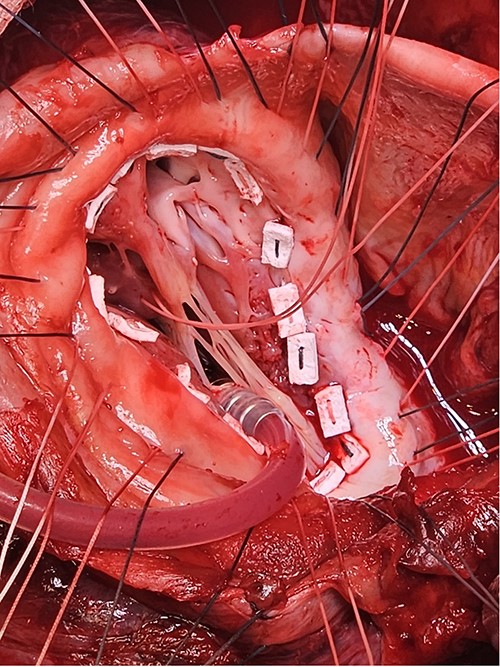

Echocardiography (Fig. 1) and cardiac magnetic resonance imaging revealed a dilated LV [left ventricular ejection fraction (LVEF) of 25%] and a large aneurysm (9.3 × 9.5 cm) involving the basal mid-inferoseptum and basal inferolateral wall with evidence of thrombus. These regions were non-viable, with transmural infarction. The mitral valve (MV) leaflets were thin but the tips, especially of the posterior mitral valve leaflet, were tethered and tented towards the LV apex resulting in severe functional MR. The left atrium (LA) was significantly dilated. The patient was admitted for medical management including aggressive diuresis. Following multidisciplinary team (MDT) discussion, surgical intervention was planned (aneurysmectomy with either MV replacement or repair). Mechanical circulatory support and cardiac transplantation were considered and deemed appropriate for rescue therapy.

Preoperative echocardiography: large LV aneurysm below the posterior mitral valve leaflet tethering it open in systole resulting in severe functional mitral regurgitation.